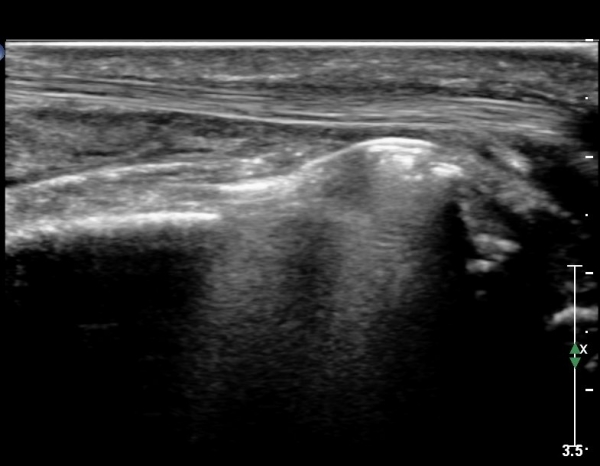

Å½ÃËÀÚ¸¦ ¾à°£ ³»ÃøÀ¸·Î À̵¿ÇÏ´Ï FPL ÈûÁÙÀÌ °íÁ¤¹°¿¡ ÀÇÇØ ¾Ð¹ÚµÇ°í ÀÖÀ½ÀÌ È®ÀÎµÇ°í ±ÙÀ§ºÎ¿Í ¸»´ÜºÎ´Â

Àú¿¡Ä¿ ºÎÁ¾ÀÌ °üÂûµÇ°í ±× »çÀÌ´Â °¡´Ã¾îÁ®¼­ ÈûÁÙÀÇ ¼Ò½Ç(ÆÄ¿­)À» ÃßÁ¤ ÇÒ ¼ö ÀÖÀ½(»çÁø 10. 11)